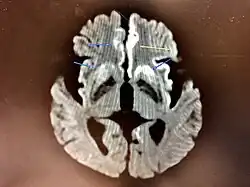

Histopathology

Testing of tissue remains the most definitive way of confirming the diagnosis of CJD, although even a biopsy is not always conclusive.[56]

In one-third of people with sporadic CJD, deposits of "prion protein (scrapie)", PrPSc, can be found in the skeletal muscle or the spleen.[57] Diagnosis of vCJD can be supported by biopsy of the tonsils, which harbor significant amounts of PrPSc; however, biopsy of brain tissue is the definitive diagnostic test for all other forms of prion disease. Due to its invasiveness, a biopsy will not be done if clinical suspicion is sufficiently high or low. A negative biopsy does not rule out CJD, since it may predominate in a specific part of the brain.[58]

The classic histologic appearance is spongiform change in the gray matter: the presence of many round vacuoles from one to 50 micrometers in the neuropil, in all six cortical layers in the cerebral cortex, or with diffuse involvement of the cerebellar molecular layer.[59] These vacuoles appear glassy or eosinophilic and may coalesce. Neuronal loss and gliosis are also seen.[60] Plaques of amyloid-like material can be seen in the neocortex in some cases of CJD.[61]

However, extra-neuronal vacuolization can also be seen in other disease states. Diffuse cortical vacuolization occurs in Alzheimer's disease, and superficial cortical vacuolization occurs in ischemia and frontotemporal dementia. These vacuoles appear clear and punched out. Larger vacuoles encircling neurons, vessels, and glia are a possible processing artifact.[58]